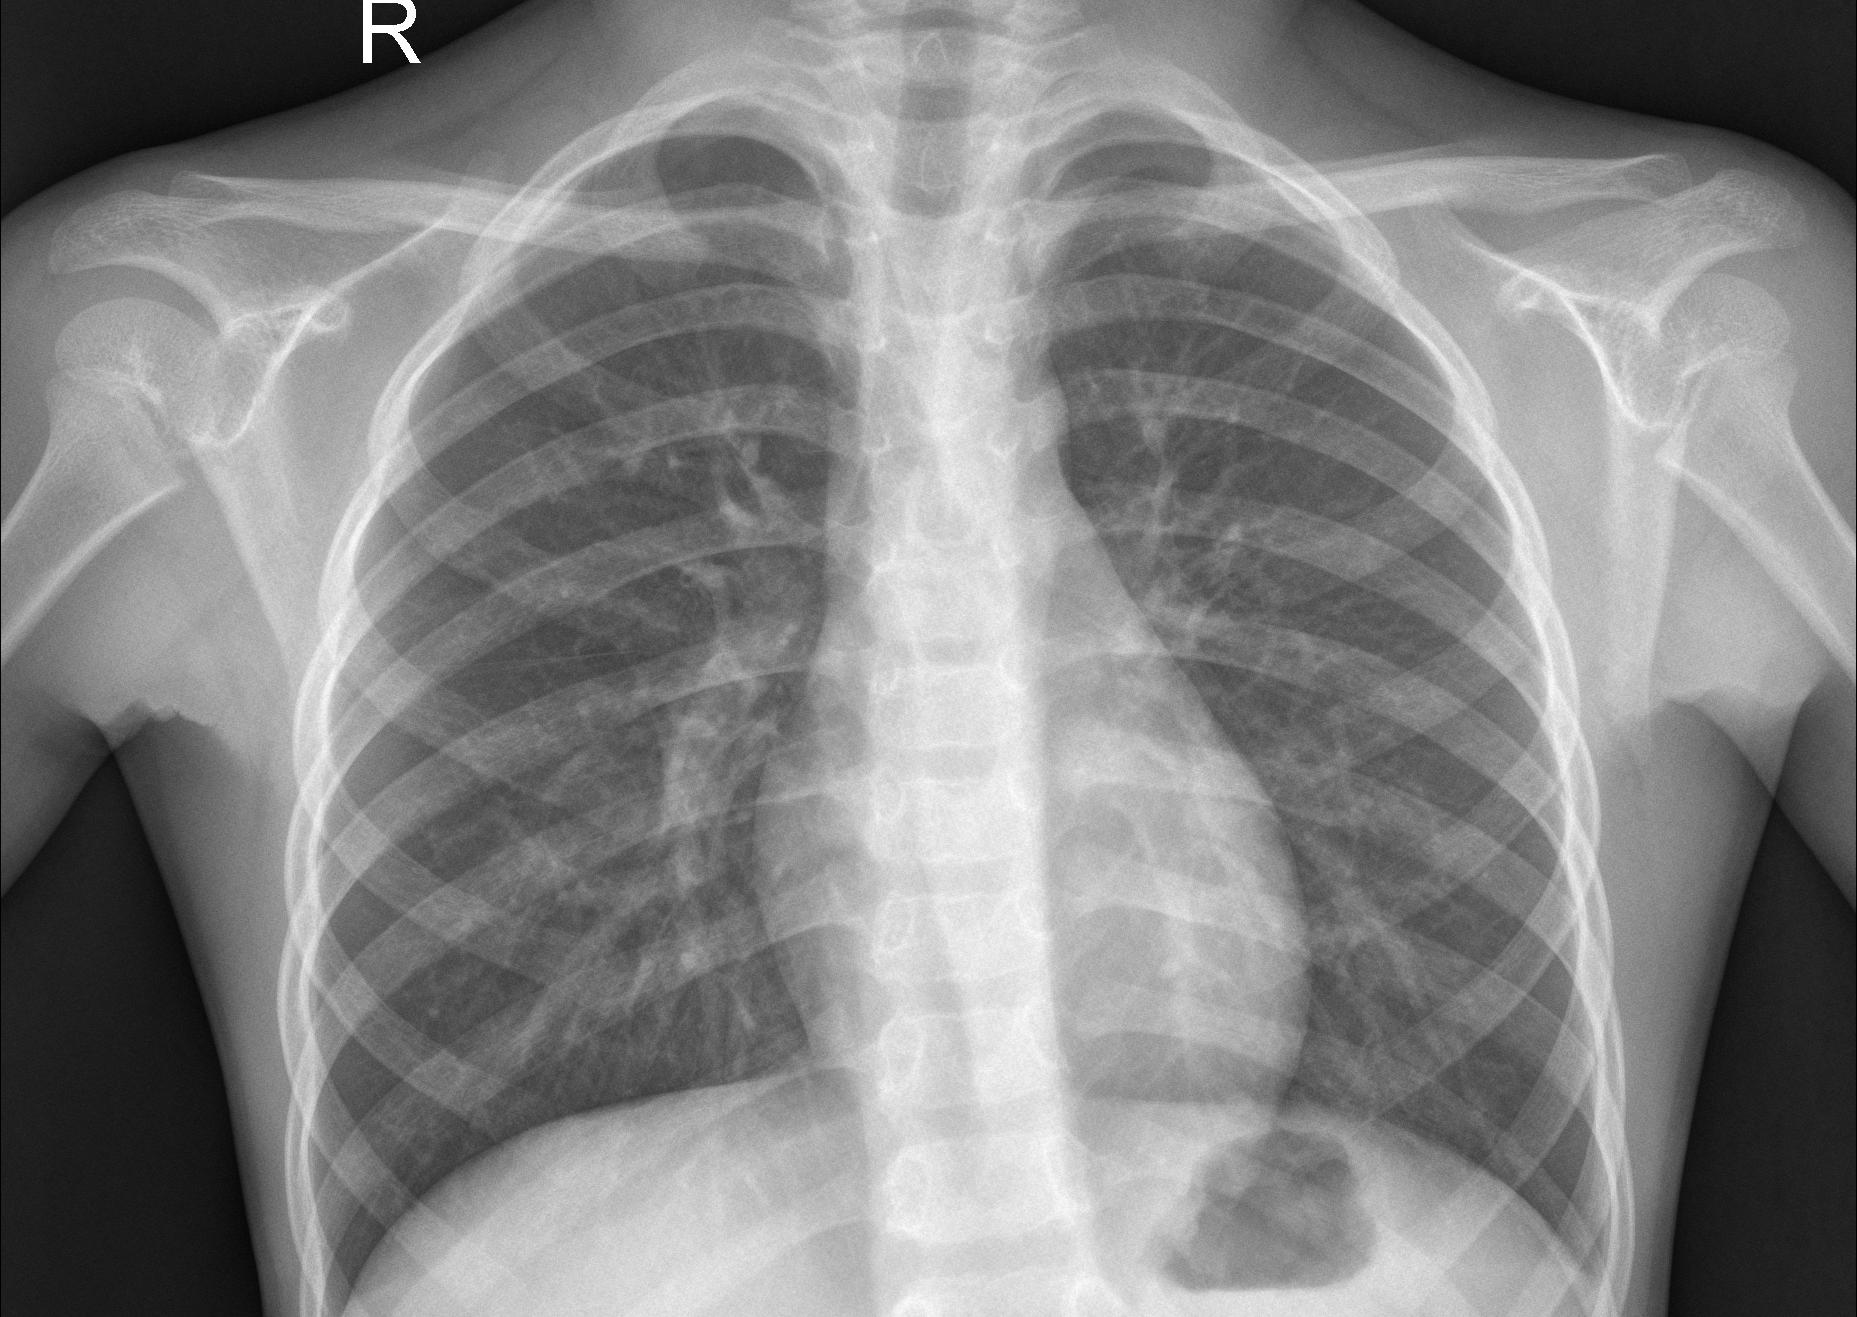

요약해보면 보자면 폐 속에 고름, 혈액 등이 차 있으면 X-ray 투과율이 떨어지며, 이로 인해 구름 같은 모양의 음영이 관찰된다면 폐렴이라 진단할 수 있다.

위의 두 사진을 비교해 보면 폐렴 환자의 X-ray는 정상에 비해 구름같은 음영이 관측된다.

이러한 현상은 폐 전체 혹은 일부에 나타날 수 있다.

[그림 1] dataset의 test/NORMAL/IM-0001-0001.jpeg

[그림 2] dataset의 test/PNEUMONIA/person113_bacteria_541.jpeg